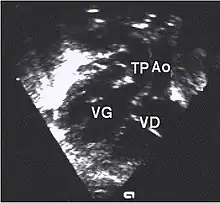

- L'échocardiographie qui est de plus en plus l'examen pratiqué en première intention. Cet examen permet d'affirmer le diagnostic en montrant les anomalies anatomiques, d'apprécier le caractère plus ou moins fonctionnel des shunts cardiaques fœtaux, de rechercher d'autres anomalies associées et dans une certaine mesure d'apprécier le retentissement de la malformation.

- Les coupes échographiques les plus utiles à cette fin sont :

- la coupe parasternale gauche grand axe : elle montre que le vaisseau issu du ventricule gauche (le plus postérieur) se dirige anormalement vers l'arrière et se bifurque précocement. C'est donc le tronc pulmonaire et non l'aorte comme normalement ;

- les coupes sous costales qui montrent bien le trajet parallèle des gros vaisseaux et leur inversion.